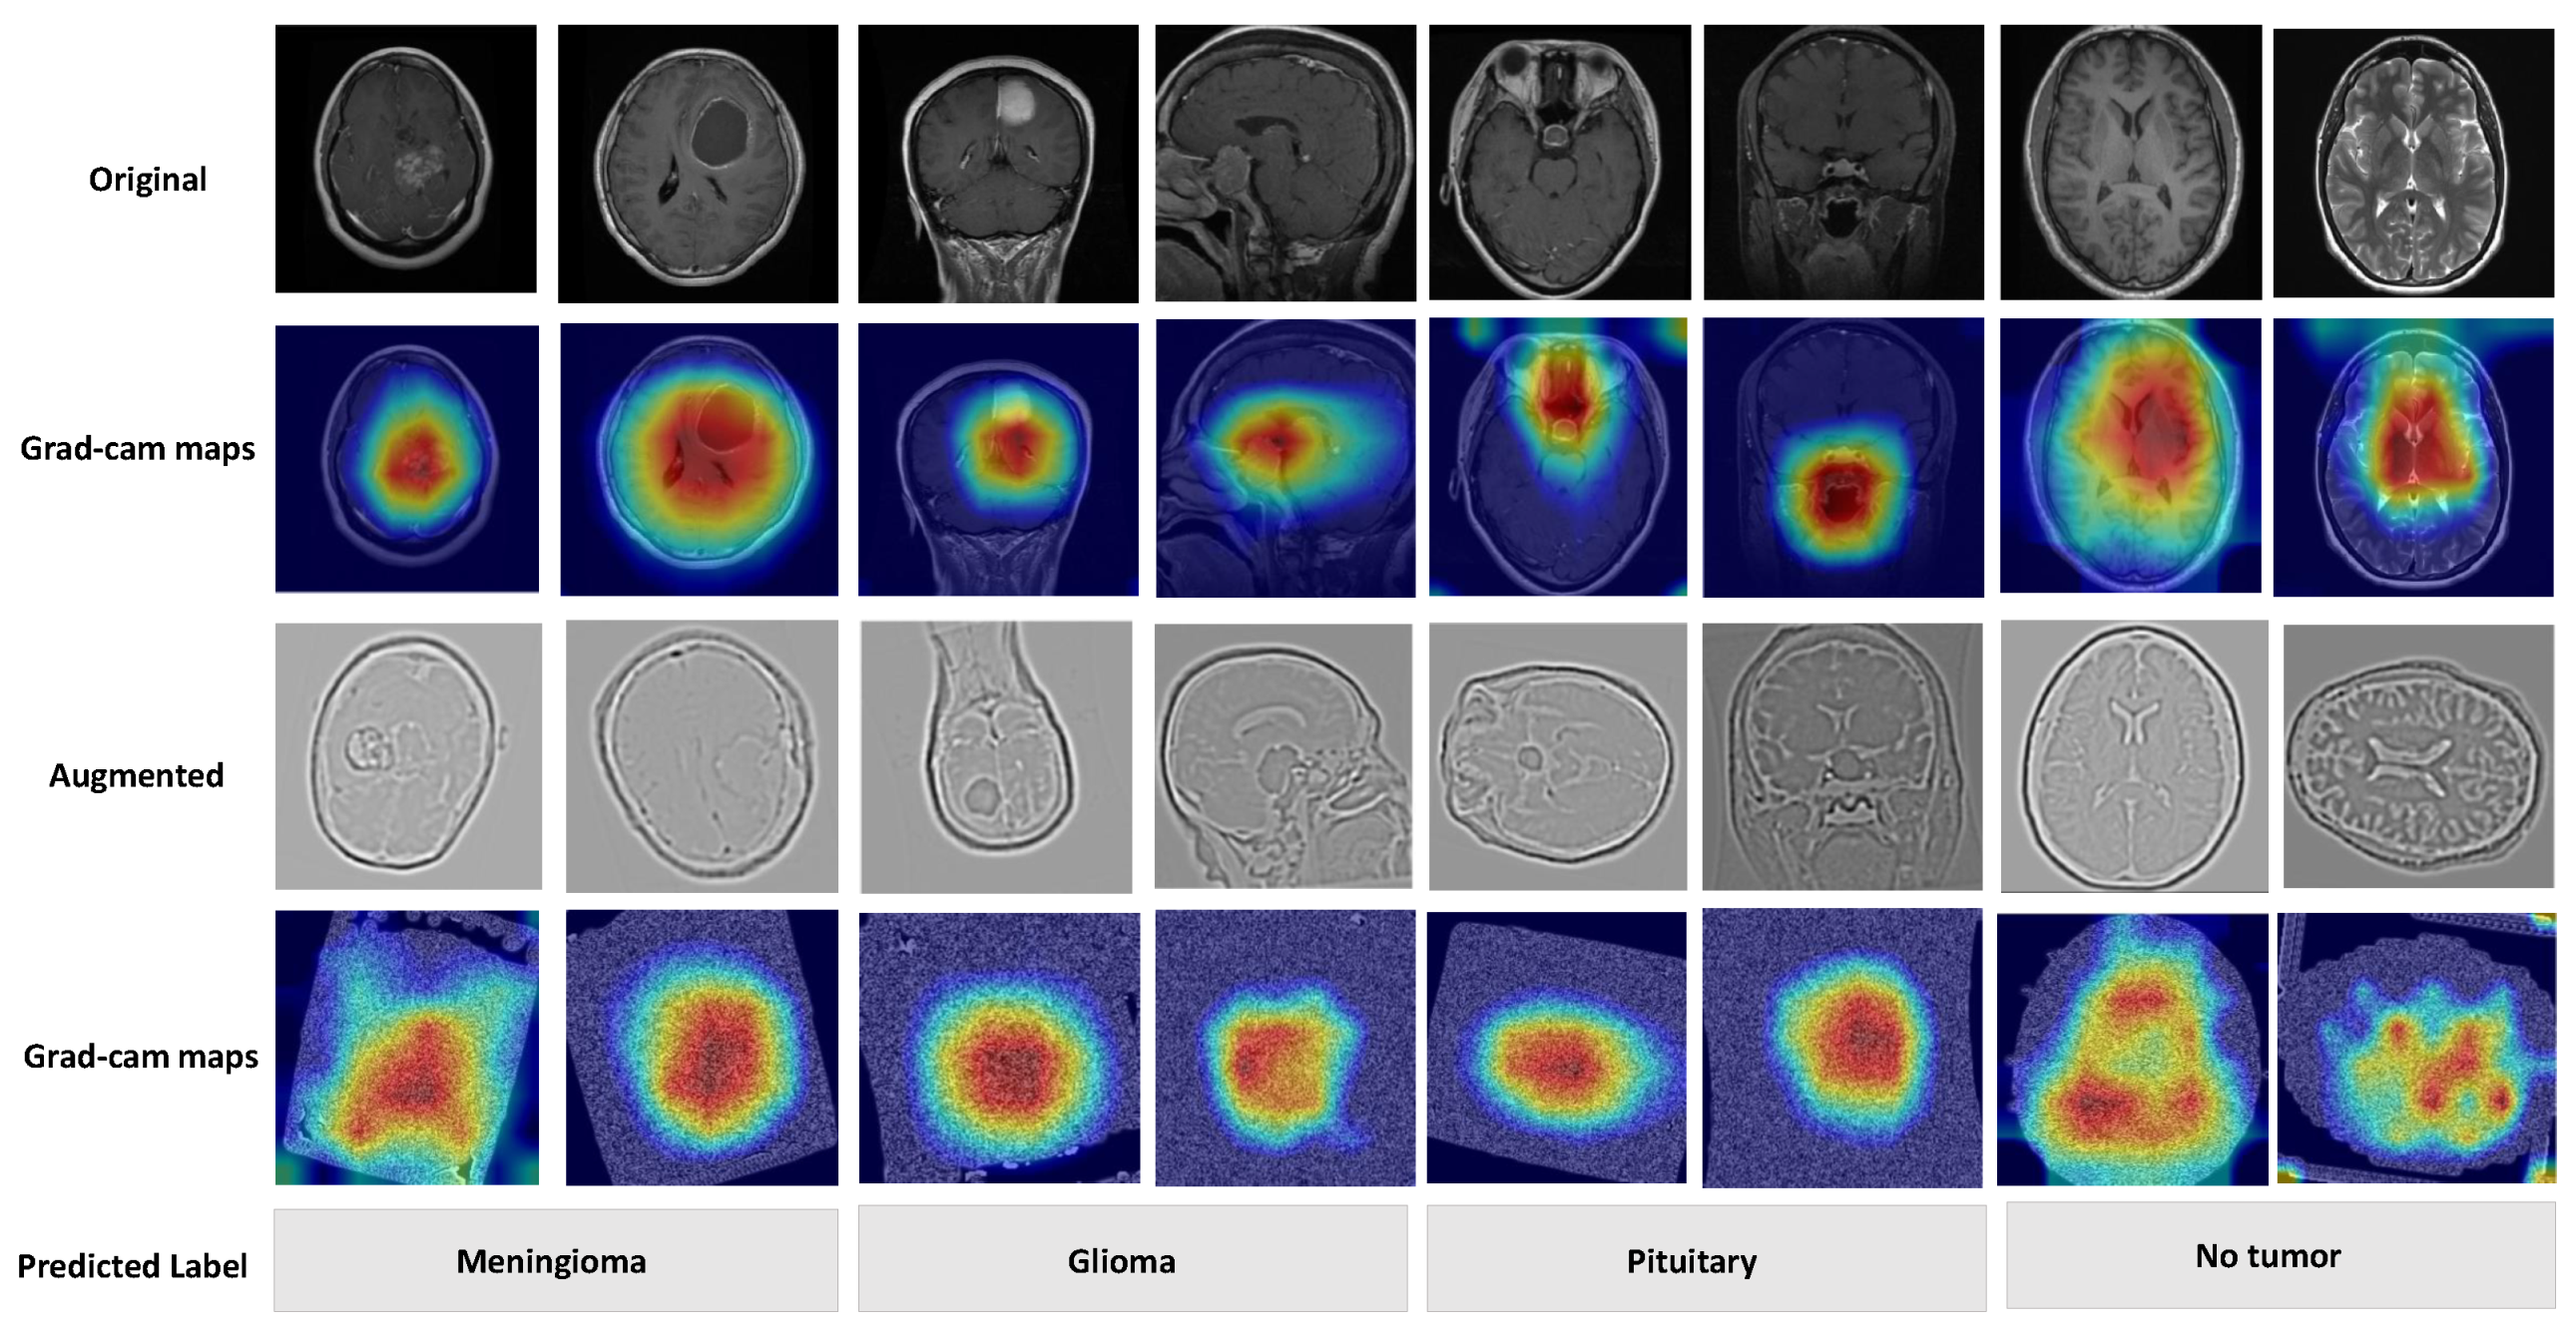

To better understand the predictions of the deep model, we used gradient-weighted class activation mapping (Grad-CAM), a widely adopted XAI technique. Grad-CAM generates visual explanations by leveraging gradient information flowing into the final convolutional layer of the deep learning model. These gradients are globally averaged to produce weights for each feature map, which are then combined to create a coarse localization heatmap. This heatmap highlights regions of the input MRI scan that most strongly influenced the model’s classification decision. This interpretation increased confidence among physicians, ensuring that the model’s decisions were consistent with clinical expectations and knowledge.

Figure 8 demonstrates how artificial intelligence interprets different tumors through MRI visualization, presenting four key diagnostic categories—meningioma, glioma, pituitary, and non-tumor. Each category is displayed through original MRI sequences and their corresponding heat map activations, where warmer colors indicate areas of heightened diagnostic significance. Through enhanced preprocessing and activation mapping, the model provides clear identification of tumor-specific features, offering an intuitive yet technically robust approach to AI-assisted neuro-oncological classification.

Figure 8. Visualization of different tumor types, showing the heat-maps for the original and augmented images (with labels). Each row displays the original MRI scan, the corresponding heatmap visualization, the augmented MRI scan with increased contrast and brightness, and the heatmap of the augmented image. Input image sample taken from the BT-3264 dataset [17].